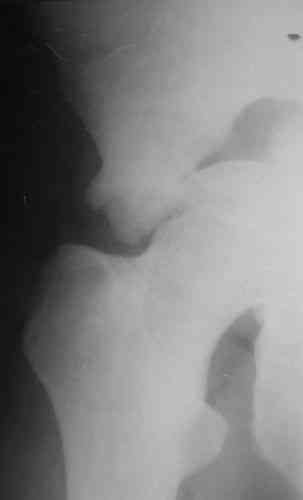

Пациентка 38 лет. В результате ДТП 02.09.06 получила поперечный перелом правой вертлужной впадины, центральный вывих правого бедра, разрыв правого крестцово-подвздошного сустава.

В одной из районных больниц вывих устранен, наложена система вытяжения по оси бедра и за вертельную область. Спустя 2 недели выполнен ВЧКО модулем "таз-бедро". Учитывая возраст пациентки и остаточный диастаз в области свода вертлужной впадины предполагается демонтаж аппарата, открытая репозиция и внутренний МОС вертлужной впадины через внутритазовый доступ.

На показанных снимках повреждение правого КПС не очень заметно...

У меня создалось впечатление( одна из РГ), что участок суставной поверхности нагрузочной зоны вертлужной впадины вдавлен( постарайтесь сделать КТ). Если это подтвердиться, то из внутритазового доступа отрепонировать будет невозможно.